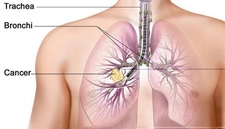

Akciğere Metastaz Yapan Tümörler